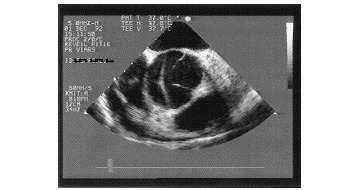

Voici les images de l’un des examens que vous avez demandés.

Question 8 - Que montrent ces images ? (une ou plusieurs réponses exactes)

On distingue sur cette coupe échographique le faux chenal de l’aorte ascendante.